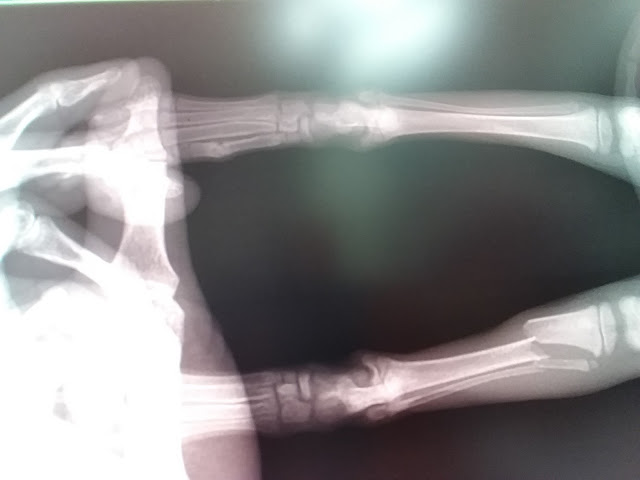

この画像は、子猫が仰向けている状態 ⇨側が頭。

両肢とも骨折箇所があります。

右肢(画像上側)は足の甲のというか中足骨4本のうち1本が折れてる。

左肢(画像下側)膝から足首の間に2本ある

脛骨(けいこつ)と腓骨(ひこつ)の両方が折れてます。

白く光ってるのは固定材料です。